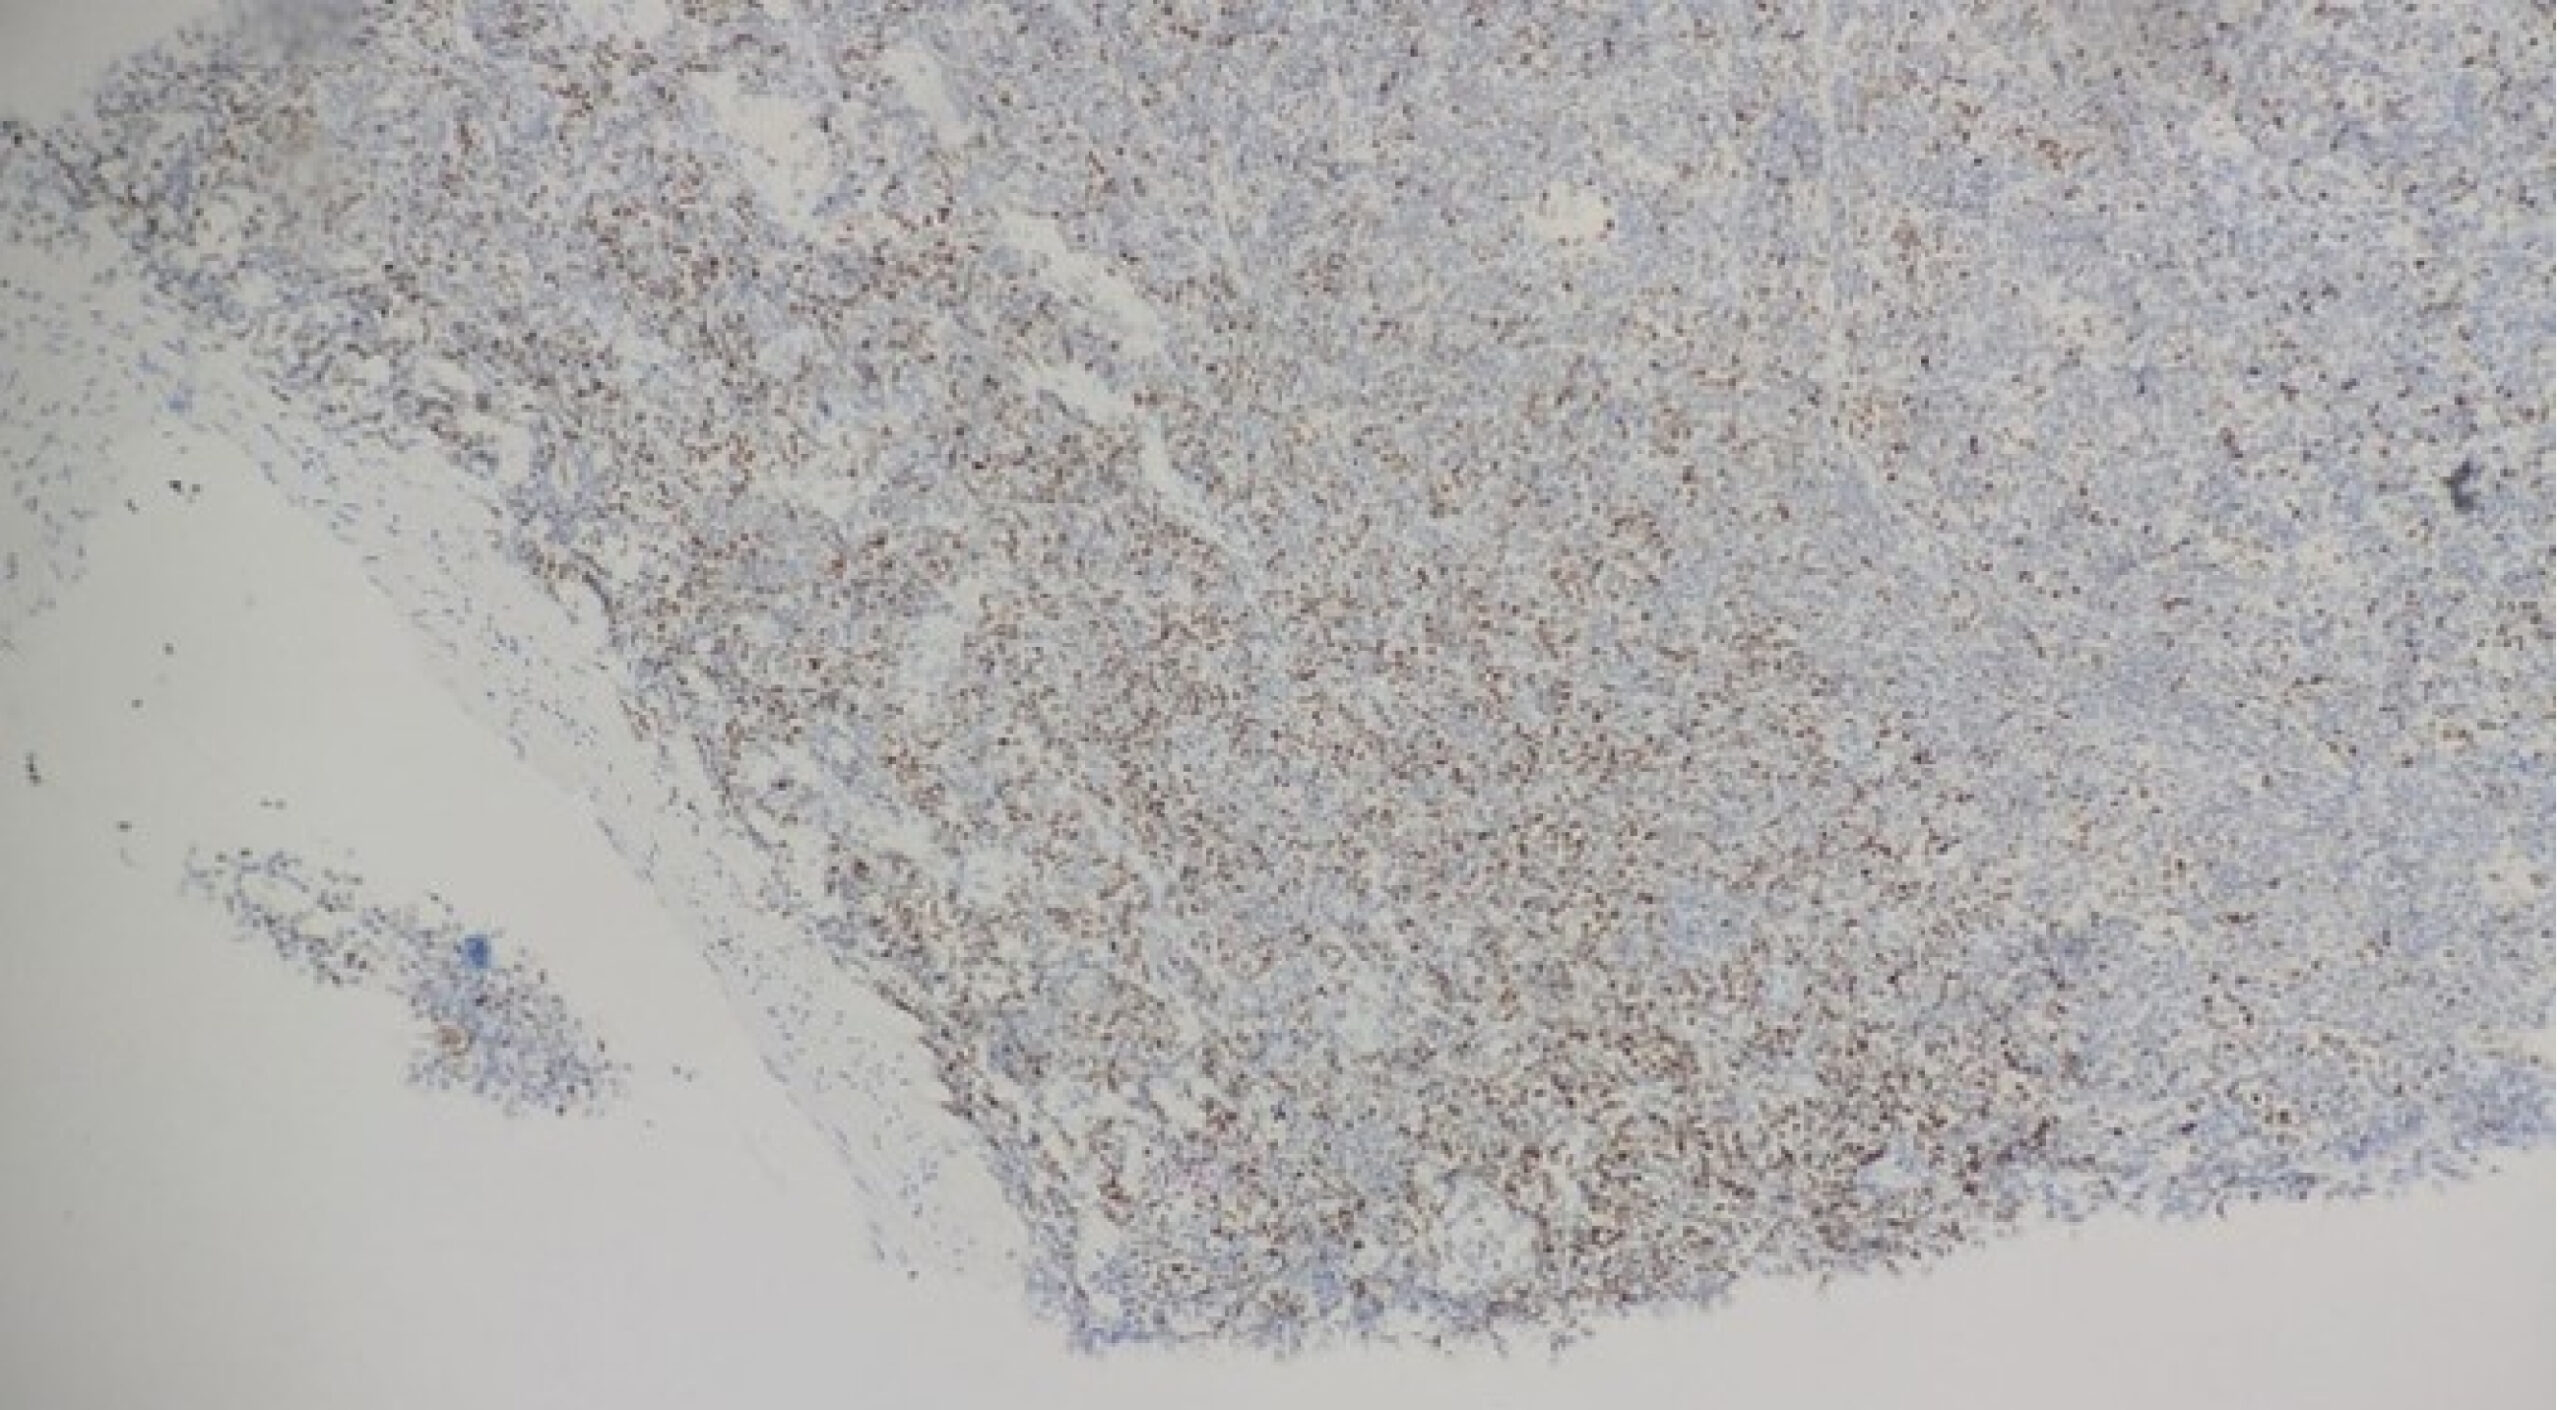

There was no indication of cancer in the first CT-guided lung biopsy, which showed a heterogeneous lymphocytic infiltrate. Due to persistent symptoms and unchanged imaging, a multidisciplinary team (MDT) recommended a repeat biopsy. The second CT-guided biopsy demonstrated malignant lymphoid cells diffusely positive for leukocyte common antigen (LCA), CD20, Pax5, Bcl2, and CD10, with scattered Bcl6 positivity (Figures 3 and 4). These findings were consistent with grade 2 pulmonary follicular lymphoma. The patient was then referred to the hematological team and started chemotherapy.

Figure 4: positive for cd20

Figure 3 shows the histopathological examination (HPE) revealing a vague follicular pattern (indicated by the arrow). Figure 4 shows a positive stain for CD20, and Figure 5 shows a weak positive stain for Bcl6.

Initial diagnostic workup, including bronchoscopy and BAL, was unrevealing. Similarly, the first CT-guided biopsy revealed a benign lymphocytic infiltrate. This highlights a key pitfall in diagnosing PPFL: the potential for inadequate tissue sampling to miss diagnostic features due to the patchy nature of lymphoid infiltrates. Only after a repeat biopsy was performed did immunohistochemistry reveal a profile consistent with follicular lymphoma (CD20+, CD10+, Bcl2+, Pax5+, LCA+), confirming grade 2 PPFL.